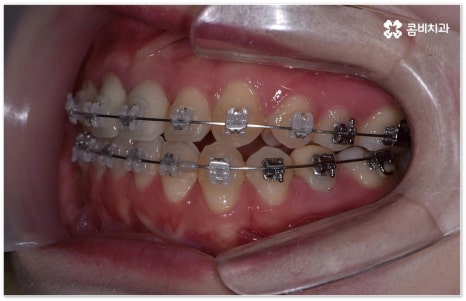

요즘 가장 많이 쓰이는 치아교정장치 인 클리피씨는 치아 색상의 세라믹 브라켓을 이용하기 때문에 심미성도 뛰어나고 자가결찰방식을 이용하여 보다 적은 힘으로 지속적이고 부드러운 치아 이동을 할 수 있도록 고안된 장치이므로 통증을 줄여줄 뿐 아니라 보통 2년 남짓 걸렸던 전체 교정 기간 역시 6개월 정도 감소시켜 줄 수 있습니다. 환자분들의 상황에 따라 내원 횟수 역시 줄일 수 있기 때문에 업무가 많이 바쁜 직장인분들의 경우에도 이용할 수 있다는 장점을 가지고 있어요.

부정교합을 개선할 때 교합이 어긋난 정도가 심하고 구조적인 원인이 커서 부분 교정이 아닌 전체 교정이 필요한 케이스인 경우라고 해도 말씀드렸던 클리피씨 교정 장치 또는 보다 심미성을 강조한 치아교정장치 들의 도움을 통해 다른 사람과 얘기를 하거나 음식을 먹을 때 브라켓이 두드러지게 드러나는 부담을 줄일 수 있으니 설측교정, 콤비교정, 투명교정, 인비절라인 등에 대해서 한 번 알아보시고 각자에게 맞는 방법으로 교정 치료를 시작해 보시길 권유드리고 있어요.